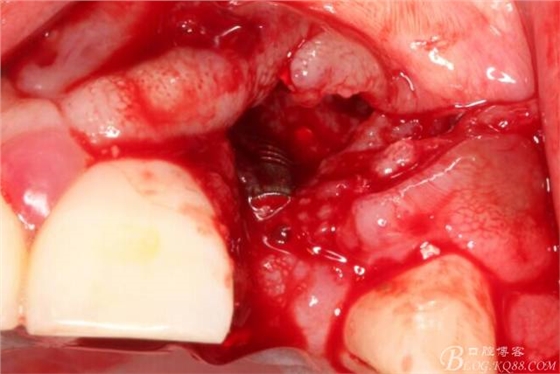

于是我果斷告知患者,手術(shù)失敗了,不能拖延,如不及時(shí)處理,炎癥繼續(xù)發(fā)展會(huì)很快波及鄰牙牙槽骨?;颊呓邮芪业慕ㄗh。切開(kāi)翻瓣,骨粉及生物膜消失了,骨吸收嚴(yán)重,幸運(yùn)的是,因?yàn)樘幚砑皶r(shí),鄰牙骨支持依然存在。

徹底掻刮。